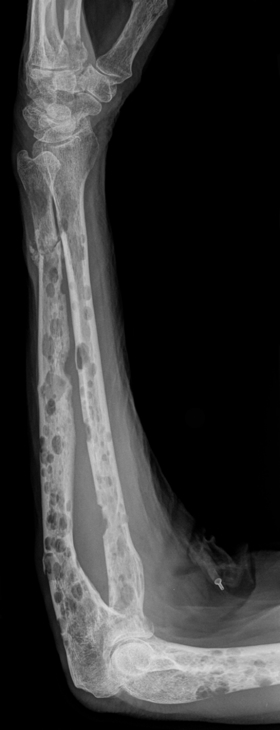

- Plasma cells activate osteoclasts → bone resorption → lytic lesions + hypercalcaemia

- Pathological fractures

- Skeletal survey or CT/MRI: Lytic bone lesions

- Bone lesions